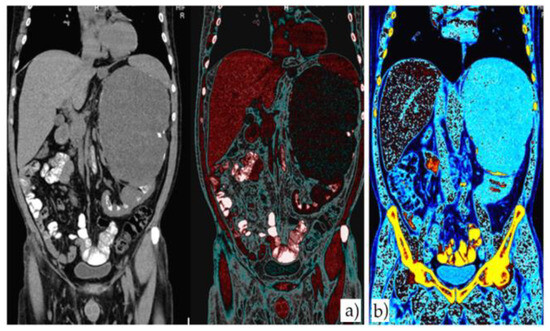

Due to the high level of creatinine presented, a native abdominopelvic CT scan was performed and the results were as follows: in the left hypochondrium and abdominal flank, a large mass was found, with an axial diameter of circa 182/136 mm and a craniocaudal diameter of approximately 212 mm, which is clearly delimited by its partially calcified walls and characterized by mainly fluid signal (including also tissue areas, septa and micronodular calcifications. The mass imprints and moves anteriorly and cranially the left postero-lateral parietal peritoneum, the spleen and the corporeo-caudal segment of the pancreas. It also imprints the regional enteric loops and the left colic flexure, being into contact through its posterosuperior pole with the left hemidiaphragm on which it discreetly ascends. The tumor seems to originate at the cortical level of the anterior valve of the left kidney, which is located in a lower position than normal. The CT scan also showed patchy calcifications arranged somewhat circumferentially at the level of both renal medullas, without obvious involvement of their cortex (nephrocalcinosis). The rest of the intra- abdominal organs had a normal appearance at the time of examination (Figure 3 and Figure 4).

Figure 3. Different color-coded coronal sections of native CT scan showing large retroperitoneal mass with an axial diameter of about 182/136 mm and a craniocaudal diameter of approximately 212 mm.